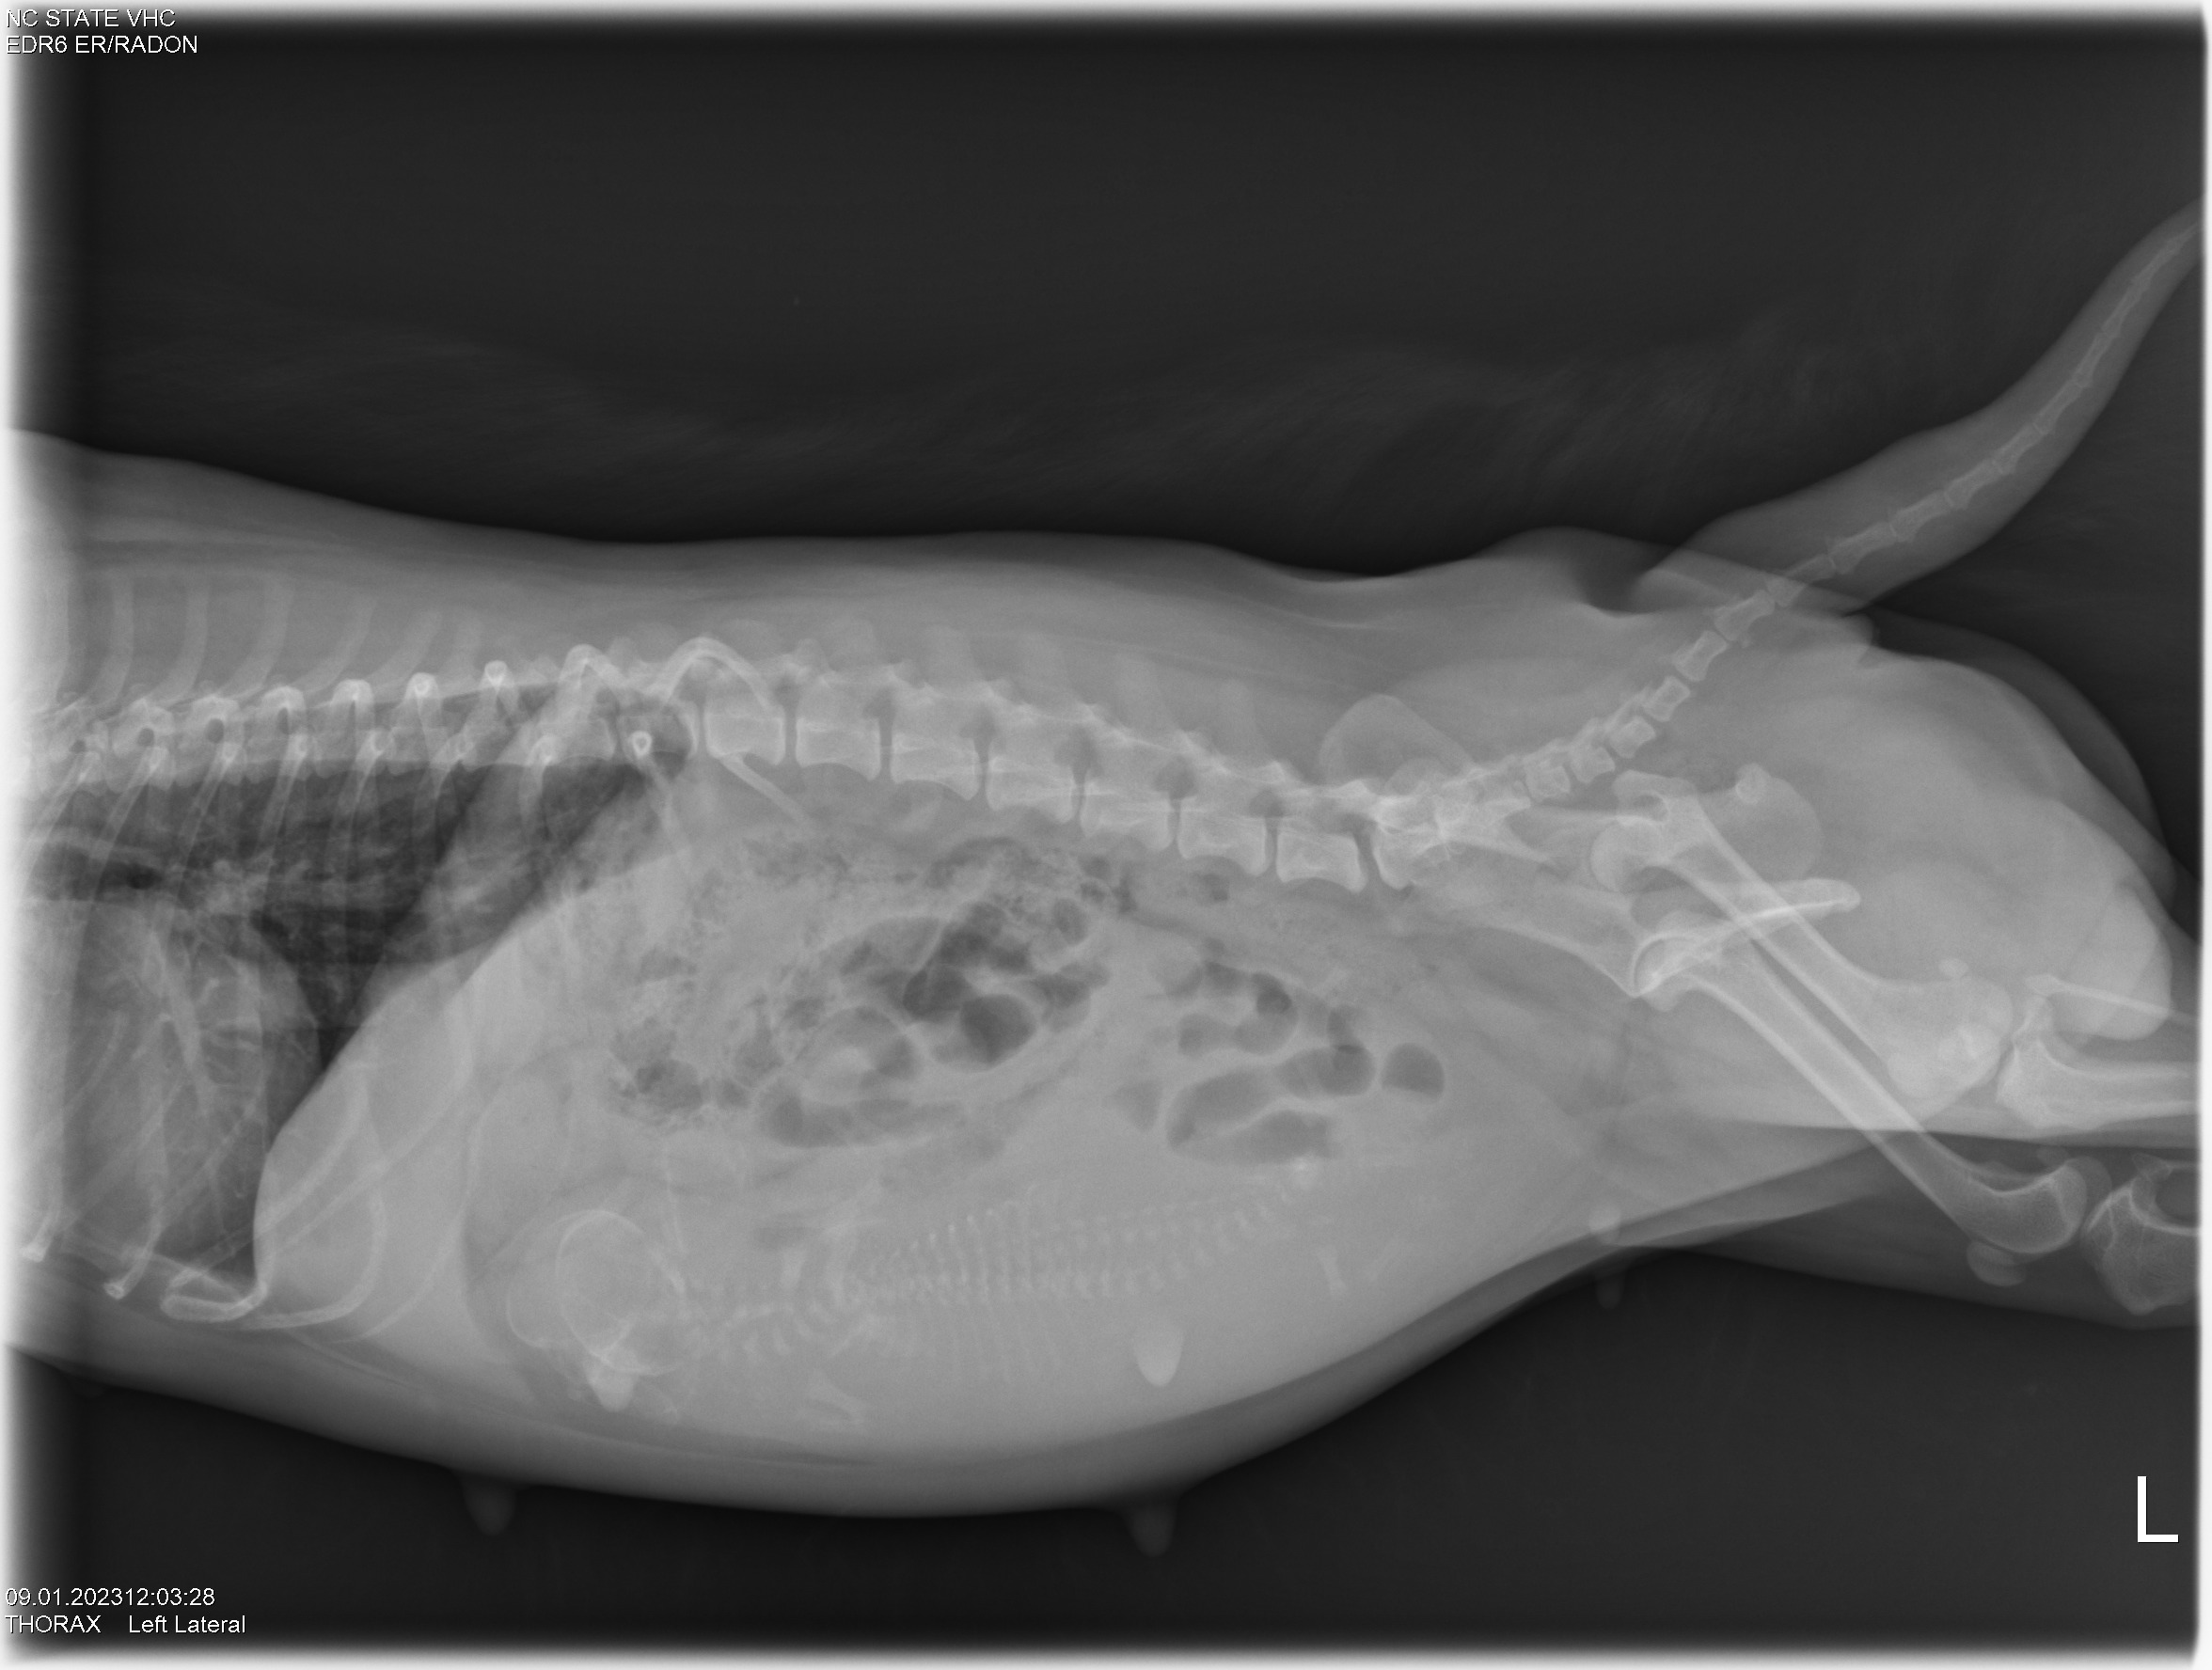

Today was x-ray day! I took both Gwynie and Siri to NC State University for abdominal x-rays. Here they are: (If you look closely, you can see the spines and perhaps the skulls of the puppies.)

Looking at the x-rays, my repro vets told me that Gwynie is carrying three puppies, and Siri is carrying two. Comparing the size of the pelvic opening of each girl with the size of the puppy skulls they are carrying, I was told for both Gwynie and Siri that the sizes are close. I was advised to have a cesarean section (c-section) for both girls. So that is what we will do.

Since Gwynie's due date is this weekend, the vets started "staging" Gwynie for a c-section. The vets checked out Gwynie's puppies using ultrasound and all looks good - good heartbeats and good GI motility. They took some blood from Gwynie and did a progesterone test. Towards the end of pregnancy, progesterone falls. Using the ultrasound results and progesterone number lets the vets decide when to do a c-section. Gwynie and I will now come back to NC State (a two-hour ride one-way) each morning for progesterone testing and ultrasound until the vets say "today is the day" for the c-section.